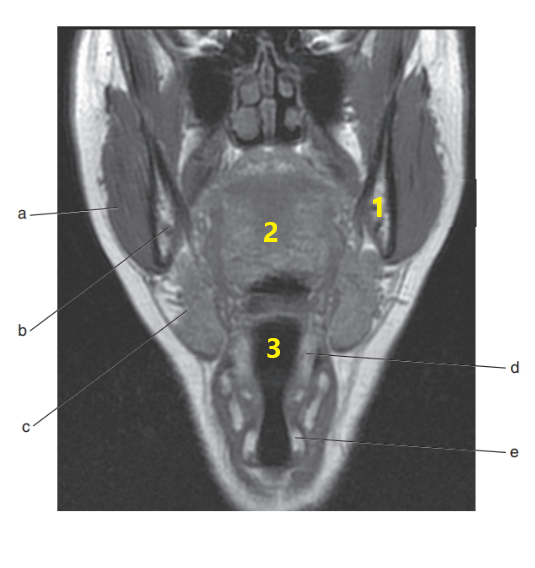

What anatomy is letter e ?

Nasopharynx

What is letter c ?

Sublingual gland

What is # 1 ?

Tongue

What is # 3 ?

Brain stem

Submandibular gland